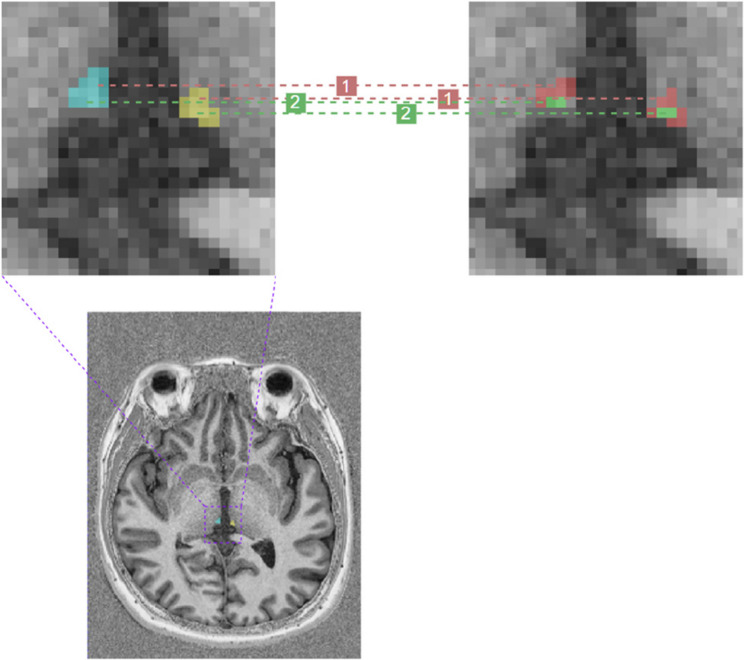

Background: The habenula (Hb) is a vital hub for the monoaminergic pathway and plays a crucial role in depression pathophysiology. However, owing to its small size and heterogeneity between individuals, there is no consensus on imaging alterations in the Hb in depression. This study aimed to examine the differences in the Hb between healthy controls (HCs) and patients with first-episode depression (FED) who were not taking any antidepressants, and to assess the value of Hb voxel cluster radiomic features in discriminating patients with FED from HCs.

Methods: This cross-sectional study included 94 participants (47 HCs and 47 patients with FED) who underwent 3-T magnetic resonance imaging. Differences in the Hb volume and T1 values between the two groups were examined. Correlations among volume, T1 value, depression severity, and age were also examined. Furthermore, a clustering-based radiomics model to differentiate patients with FED from HCs was developed and validated.